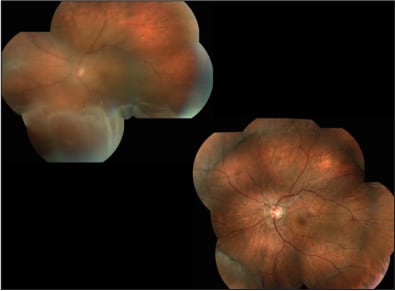

Successful retinal reattachment surgery requires sealing of retinal breaks and relief of vitreoretinal traction.5 SB is the most well-established technique and has the longest available published follow-up data.6 SB is a reasonable choice for most primary retinal detachments (Figure 1). Relative contraindications to SB are primarily related to technical issues with placement of the buckling elements. They are listed in Table 1.

Figure 1. Pre- and postoperative image of a phakic rhegmatogenous RD, which was treated with an encircling scleral buckle. The retina was completely reattached.